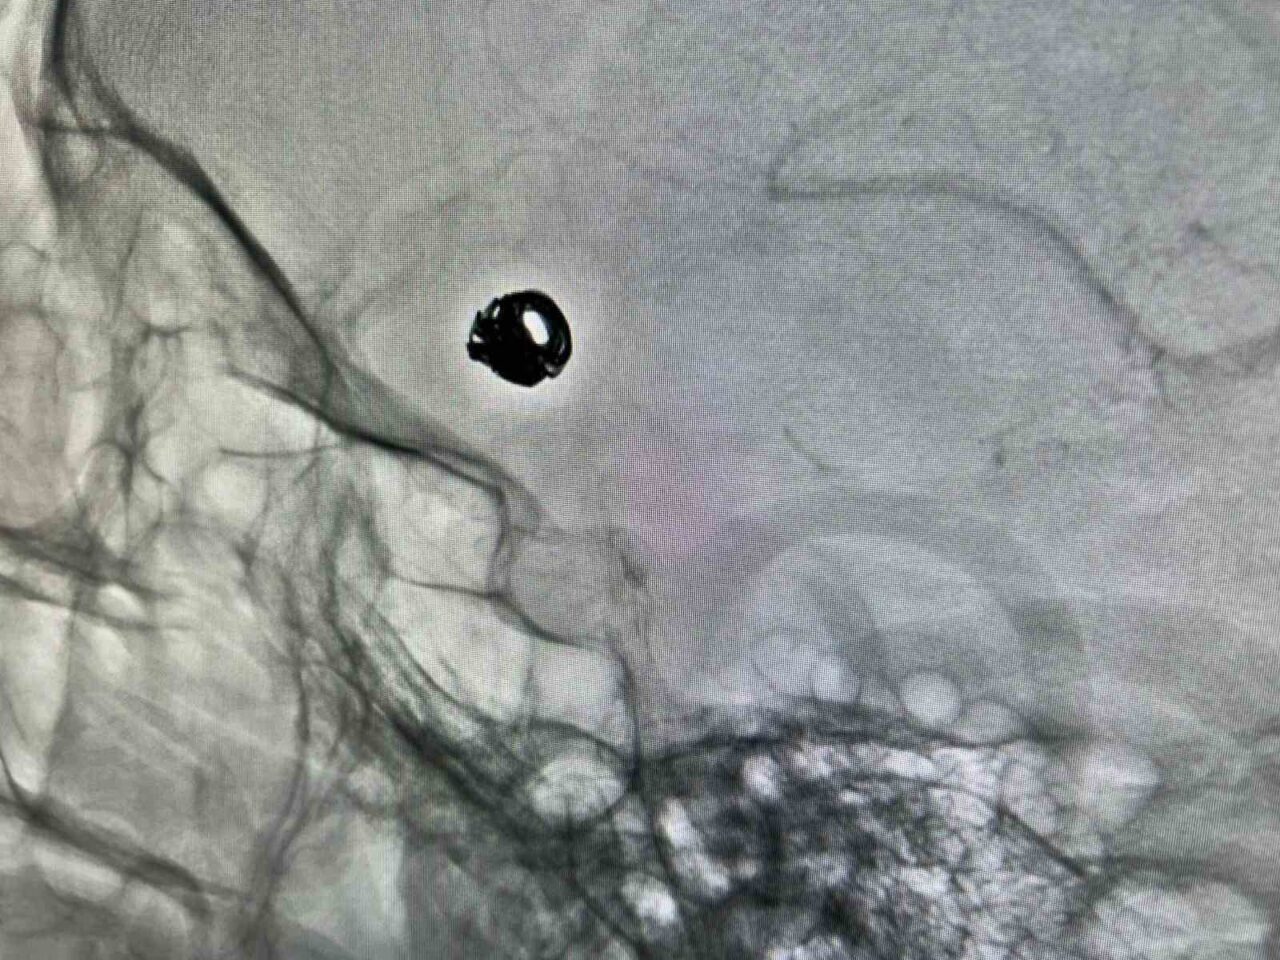

Kapalı anjiyografik yöntemle hastanın kasığından damarların içine girilerek anevrizmanın tedavisi için platin teller (coil) kullanıldı. Yapılan takipler neticesinde, hastanın sağlık durumunun giderek iyileştiği bildirildi.

Hastane Başhekimi Doç. Dr. Remzi Sarıkaya, “Hastamızın dış merkezdeki tomografi incelemesi sonrasında beyin kanaması ve anevrizma tespit edildi. Hızla ambulans ile Van Eğitim ve Araştırma Hastanesi’ne taşındı. Kasıktan yapılan müdahale ile beyin damarlarına ulaşıldı ve endovasküler tedaviye uygun bulunarak işlem yapıldı. Yaklaşık 1,5 saat süren işlemin ardından anevrizmanın içi platin tellerle kapatıldı. Bu uygulama ile yeniden kanama riski ortadan kaldırıldı” şeklinde bilgi verdi.

Girişimsel Radyoloji Uzmanı Dr. Berat Demiral da hastanın Van Eğitim ve Araştırma Hastanesi’ne sevk edilme sürecini ve yapılan anjiyografi işlemini aktardı. “Hastada yapılan tomografi sonucunda beyin kanaması tespit edildi ve anjiyo işlemi gerçekleştirildi. Gerekli müdahale ile anevrizmanın tedaviye uygun olduğuna karar verildi. İşlem sırasında anevrizmanın ağzına mikrokateterle ulaşarak, içine platin teller yerleştirildi ve kan akışının durdurulması sağlandı” dedi.